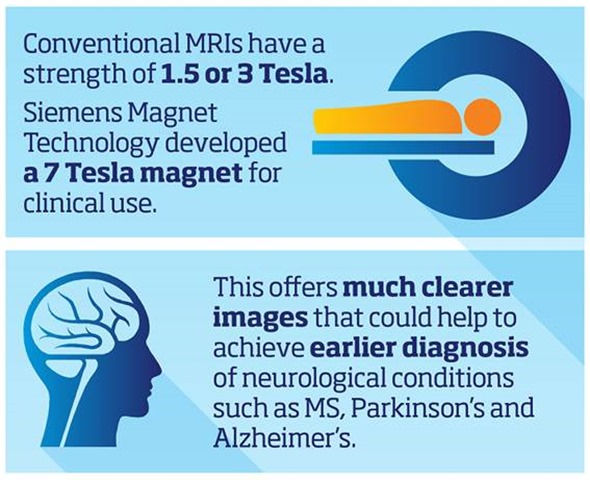

What strength do most MRI scanners operate at and why have Siemens Magnet Technology (SMT) developed an ultra-high magnetic field (UHT) 7 Tesla (7T) system?

Most MRI scanners operate between 1.5 Tesla and 3 Tesla. Due to benefits of the increased resolution at higher filed strengths SMT have developed a ground breaking 7 Tesla system, the MAGNETOM Terra. This new system has been designed to meet the demands of both researchers and clinicians.

This allows researchers to identify lesions and bleeds more easily, and the specific areas of the body affected - potentially enabling unprecedented insights into hard-to-diagnose conditions.